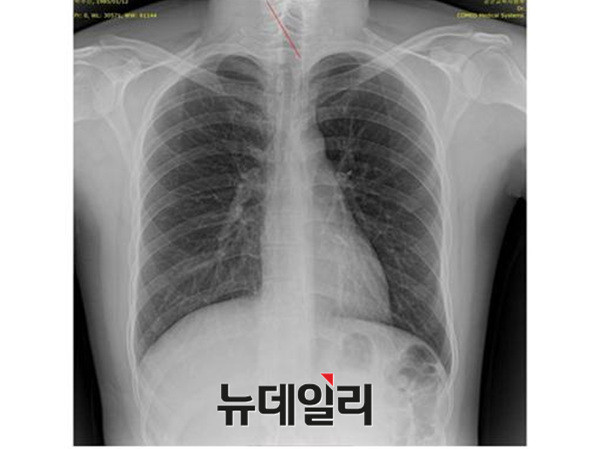

“자생한방병원 엑스레이와 공군 엑스레이 영상에 나타나는 심장의 크기와 모양, 폐의 음영 등이 육안상으로도 확연히 다르다. 따라서 자생한방병원에서 엑스레이를 촬영한 사람은 박주신이 아니며, (박주신씨의) 대리인이 서울병무청과 세브란스 병원의 MRI촬영에 지속적으로 개입했다고 밖에 볼 수 없다.”